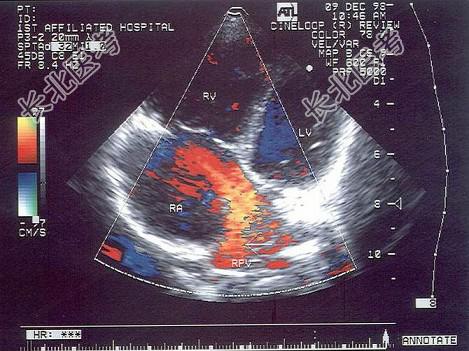

- 单项选择题该病例最有可能诊断为(   )

A、部分型心内膜垫缺损

B、原发孔房缺

C、继发孔房缺

D、部分性肺静脉畸形引流

E、冠状静脉窦隔缺损